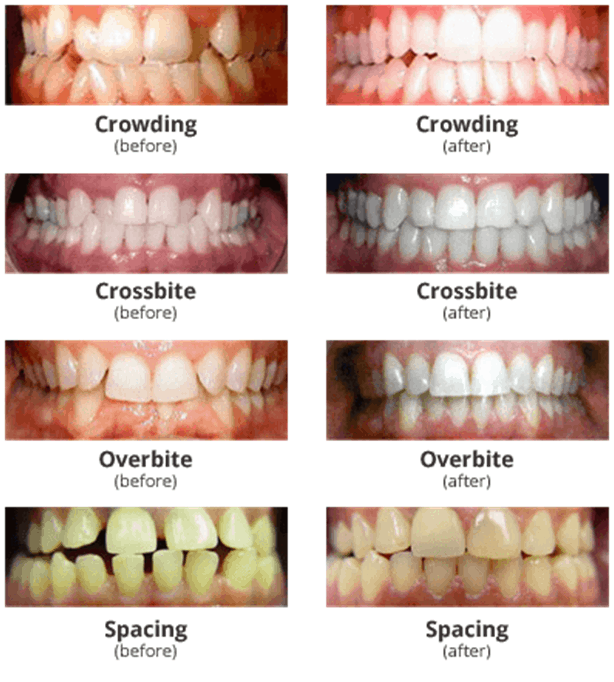

Crooked or Crowding Teeth Treatment before & after photos – The Perfect …

Orthodontic Treatment Before After Stock Photo – Download Image Now …

How To Correct Overbite With Braces : Need brace, fix teeth with brace …

Crooked Teeth Treatment | Oppenheim Signature Smiles

How To Fix A Crossbite In Adults : (PDF) Unilateral canine crossbite …

What Causes Crooked Teeth? | Berkman & Shapiro Orthodontics

Crowded Teeth – Manhattan Bridge Orthodontics

Do You have Crooked Teeth?